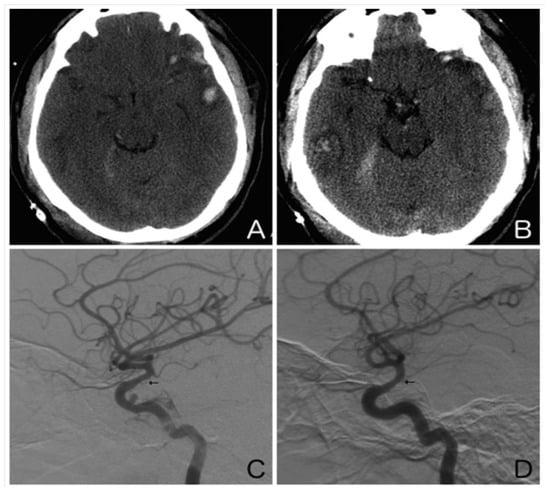

5. Post-Traumatic Vasospasm